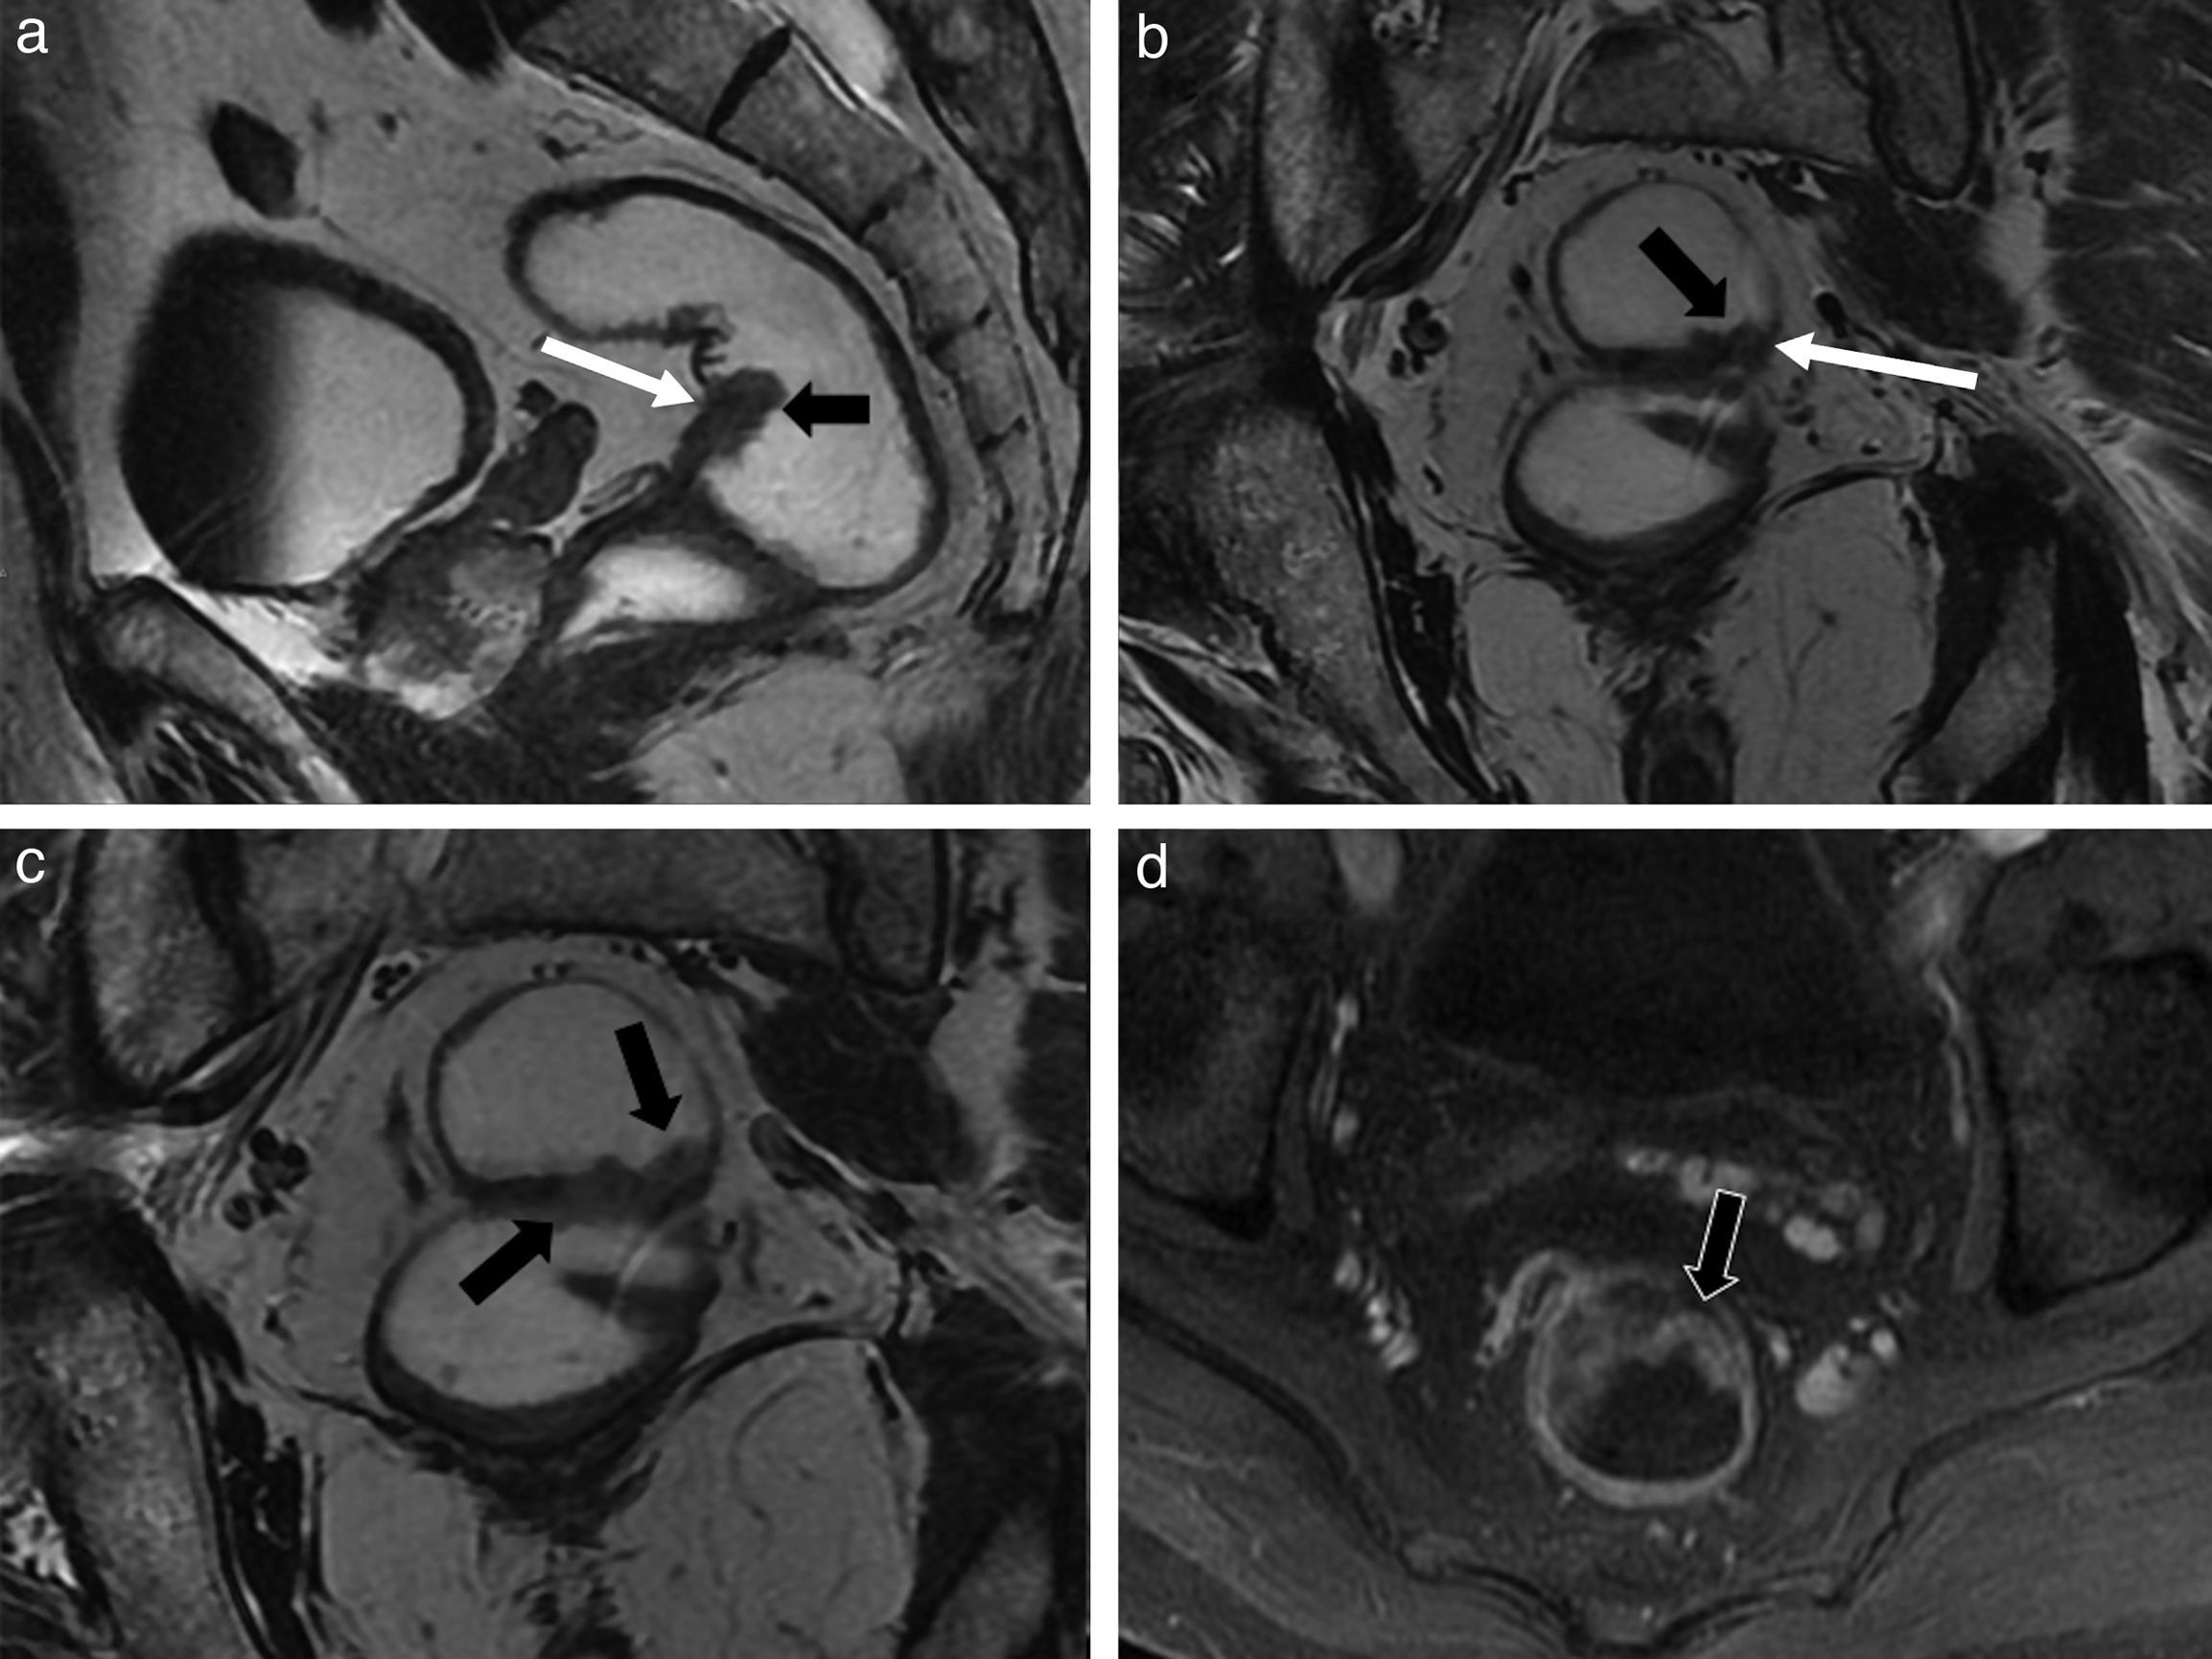

Benign anorectal disease comprises a broad group of processes with very diverse origins; these processes may be congenital or acquired as well as inflammatory or tumor related. However, benign anorectal disease has received less attention in the scientific literature than malignant disease. We present an image-based review of the most common benign diseases of the anus and rectum. In this first part, we review the anatomy of the region and provide a brief description of the peculiarities of the high resolution protocol that we use with 3.0 T MRI. We go on to describe the most common benign anorectal tumors and developmental cystic lesions, together with their differential diagnoses, as well as congenital and acquired anomalies of the anorectal sphincter complex.